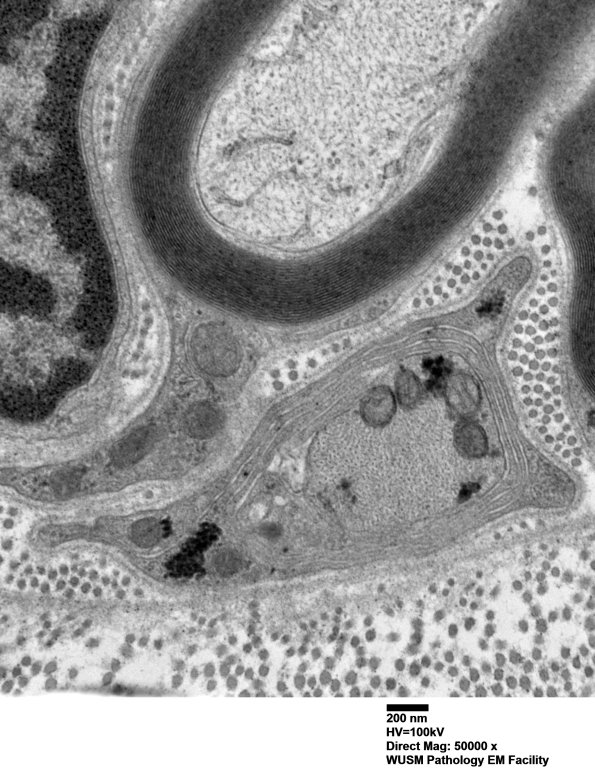

Multiple images of this cluster of immature, likely regenerative axons, collections of Schwann cell cytoplasm and small axons which represents pathologic alteration and not normal structures. Notice the intact basal lamina which surrounds the entire collection of elements. (Electron micrographs)